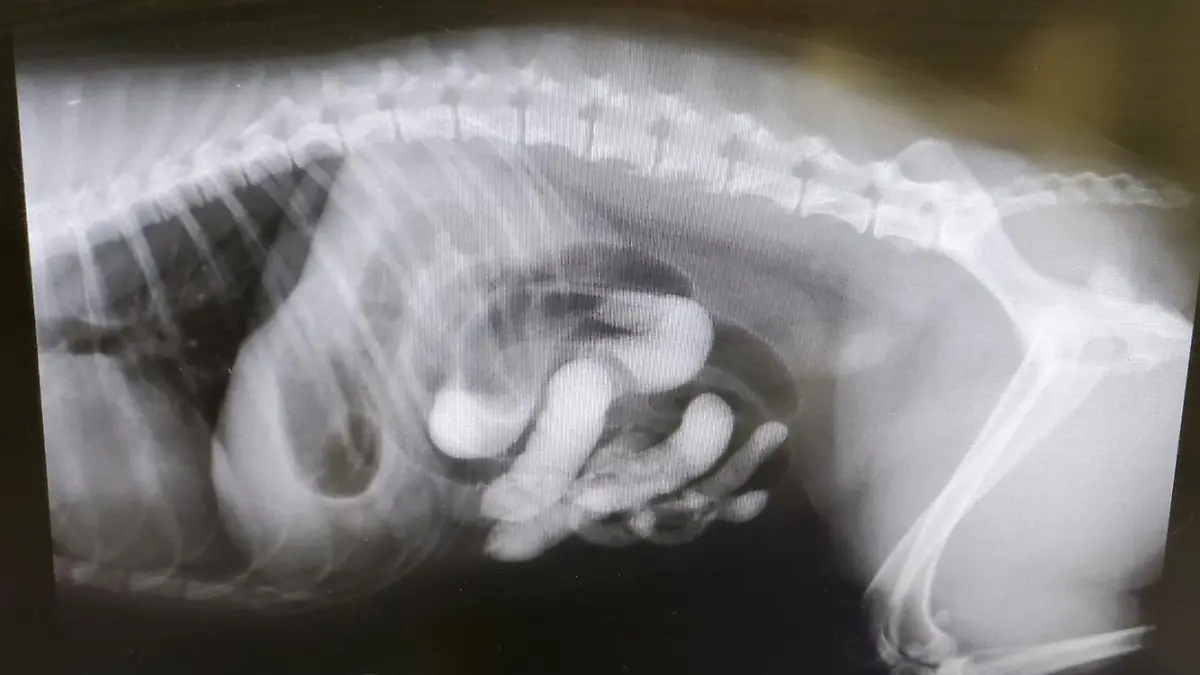

Darauf möchte nun ein Paar aufmerksam machen, nachdem sein Hund beinahe an dem geschluckten Sand gestorben wäre. Im Röntgenbild ist die Menge Sand zu sehen, die operativ entfernt werden musste.